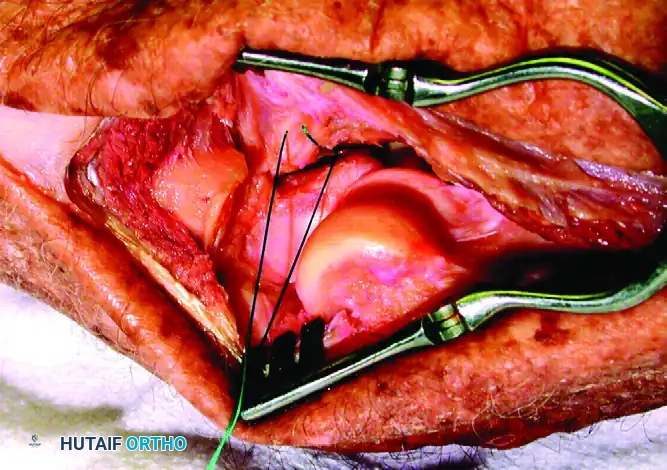

FIGURE 57-67 B: The anterior capsule is captured by nonabsorbable sutures and secured through drill holes in the fracture bed of the coronoid.

Small fragments cannot accept screws. Instead, they are reduced and fixed using heavy nonabsorbable sutures. The sutures are passed through the anterior capsule and the coronoid fragment, then shuttled through drill holes exiting the posterior aspect of the proximal ulna (olecranon). Tying these sutures posteriorly effectively anchors the anterior capsule and coronoid tip back to their anatomic bed, restoring the anterior soft-tissue buttress.

FIGURE 57-62 A: Small coronoid fracture fragments and the attached anterior capsule can be securely fixed with transosseous sutures passed through the proximal ulna.